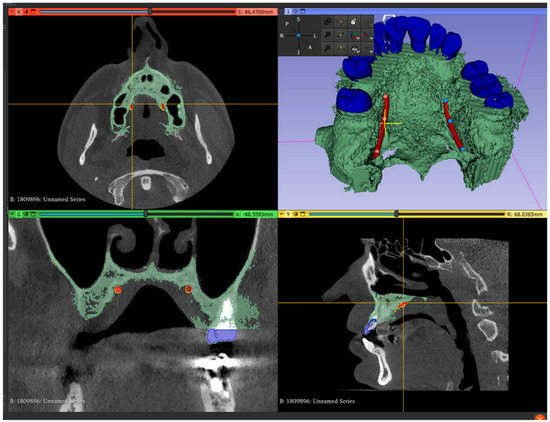

- Mark the right and left greater palatal artery pathways by using the curve tool on the “Markups to Model” module (Modules: Markups to Model: Curve). Check the coincidence of both the right and the left pathways and anatomical bone landmarks in all section views and in the 3D-reconstruction view (Figure 2);